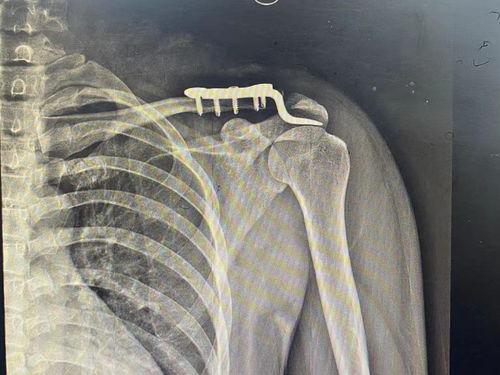

• 肩锁关节脱位图片,图解与概述

最近有个朋友不小心摔了一跤,结果肩锁关节脱位了。这可真是让人心疼啊!肩锁关节脱位,听起来是不是有点陌生?别急,今天我就带你来详细了解一番,让你对这个神秘的关节有个清晰的认识。而且,我还准备了一些肩锁关节脱位的真实图片,让你直观地感受一下这个问题的严重性。肩...